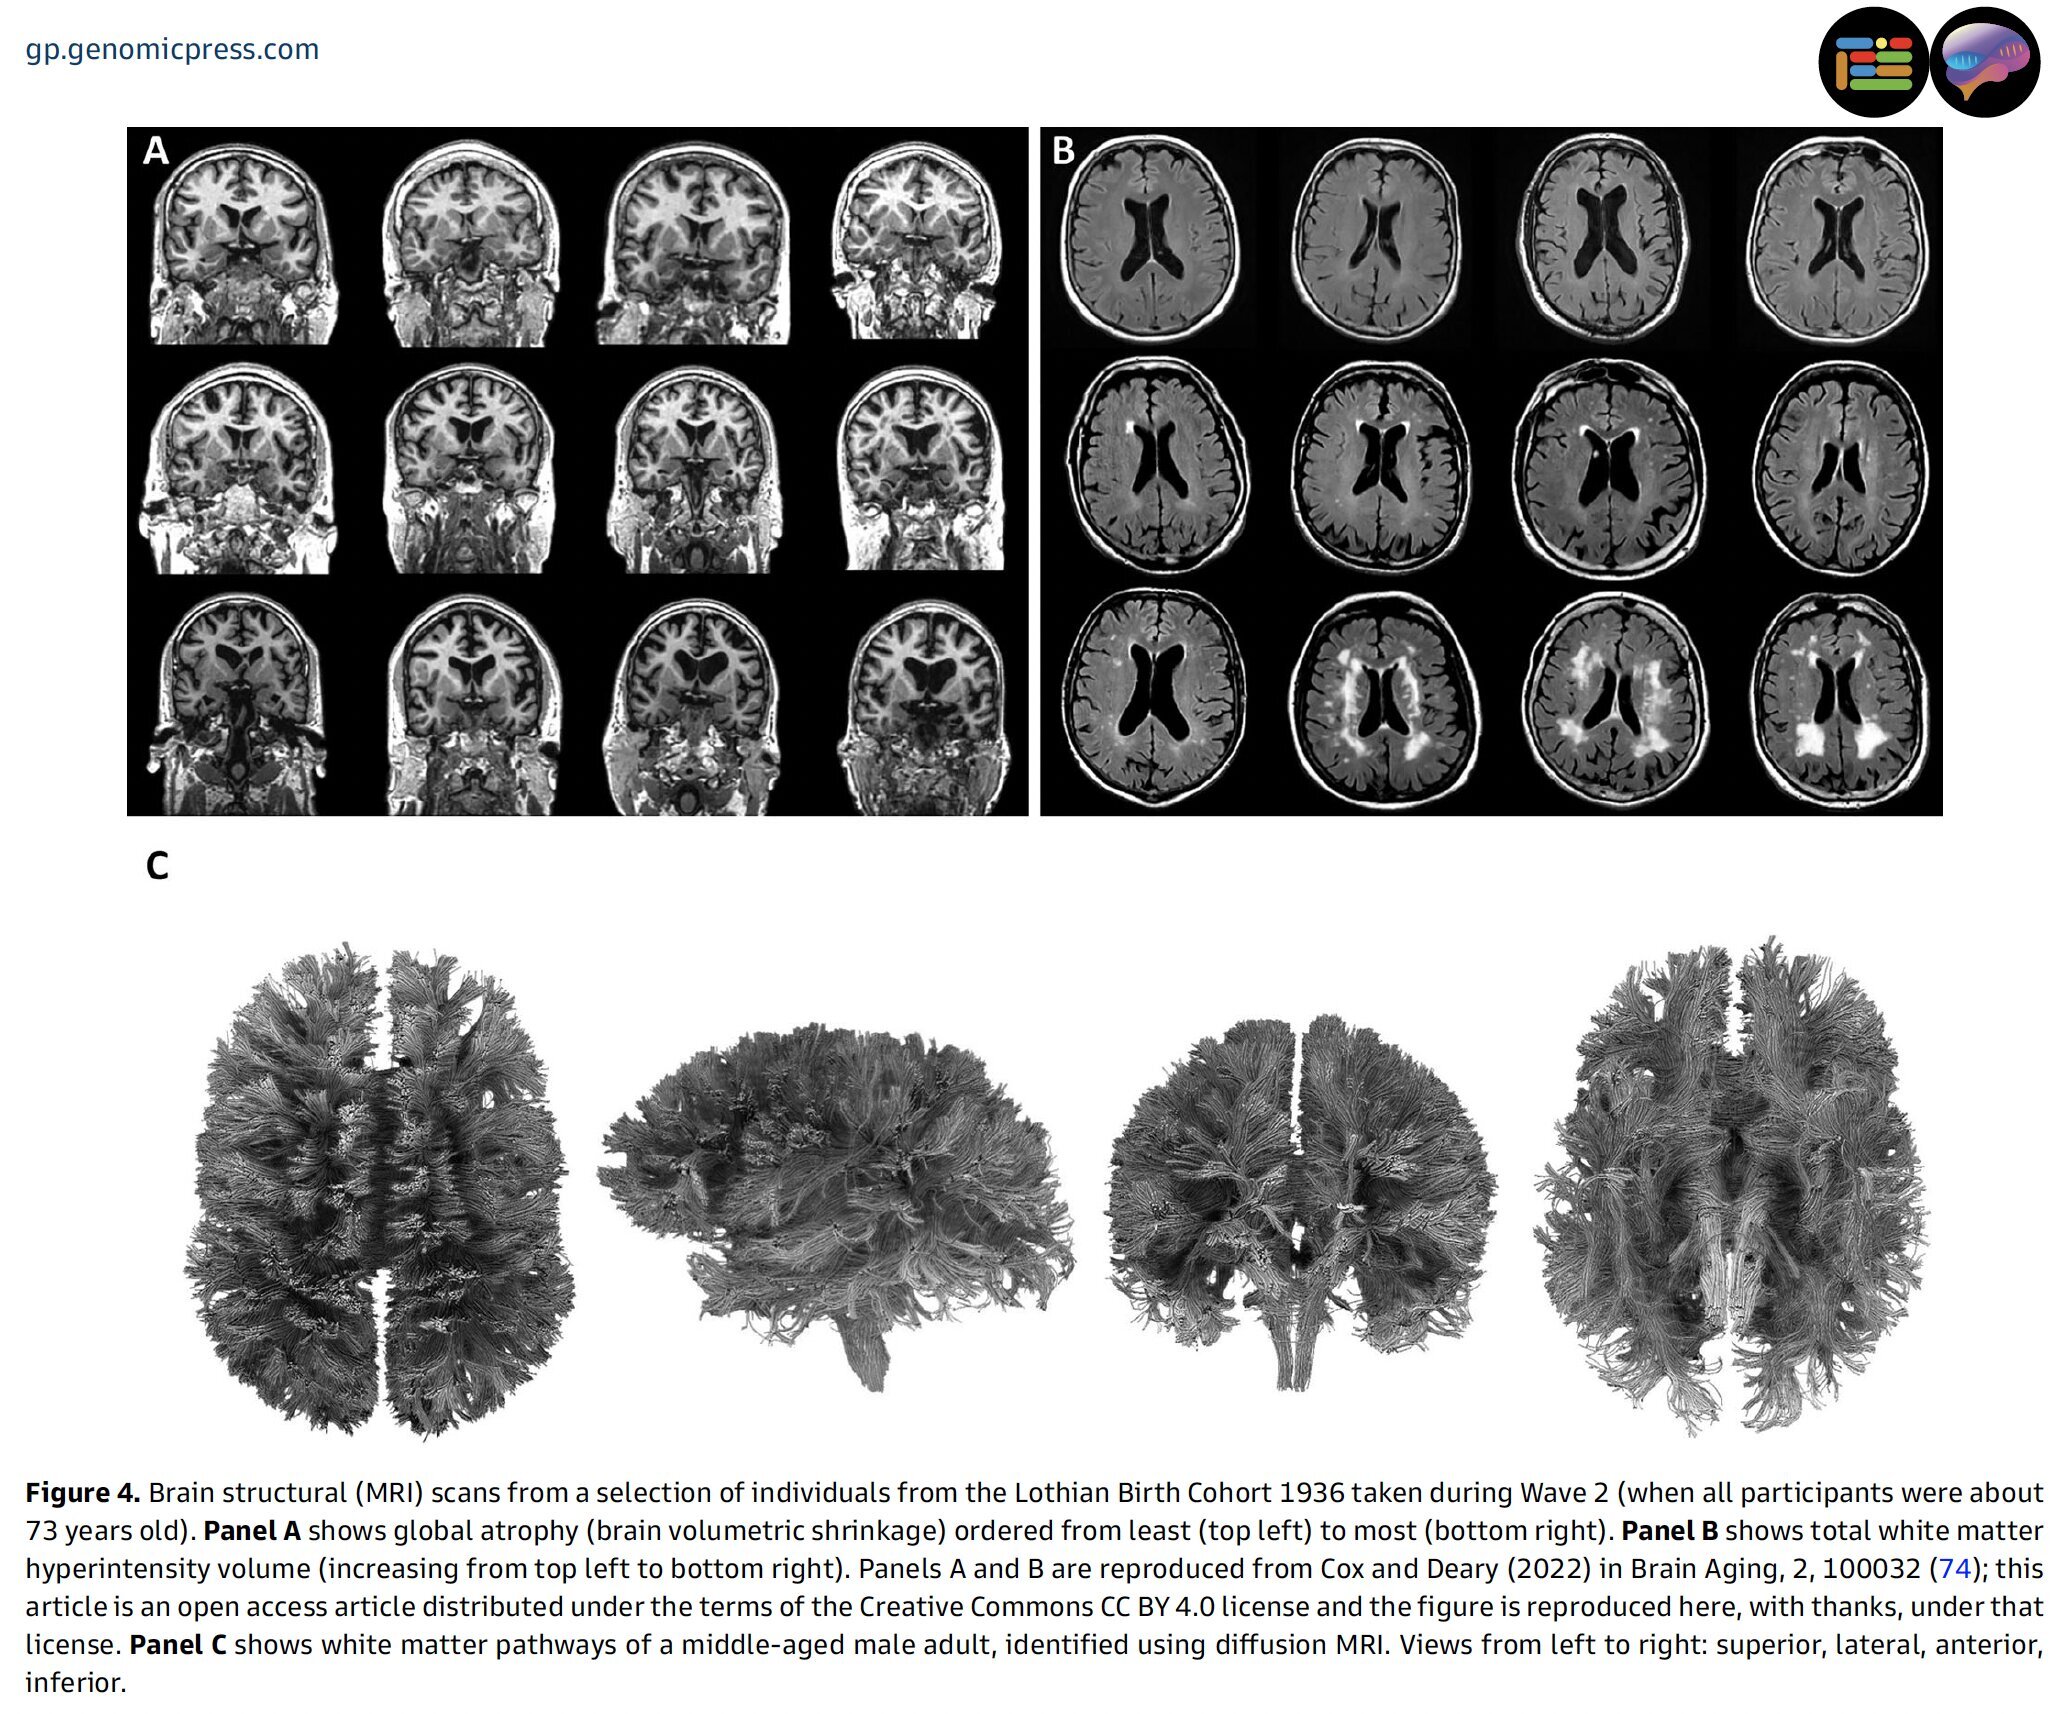

Исследование также показало, что старение мозга протекает по-разному у людей одного возраста. Особенно интересны результаты, касающиеся вариаций в здоровье мозга, выявленных с помощью передовых методов визуализации. Эти данные открывают возможности для изучения факторов, которые могут повлиять на различия в мозговом здоровье и, возможно, быть изменяемыми с помощью образа жизни.